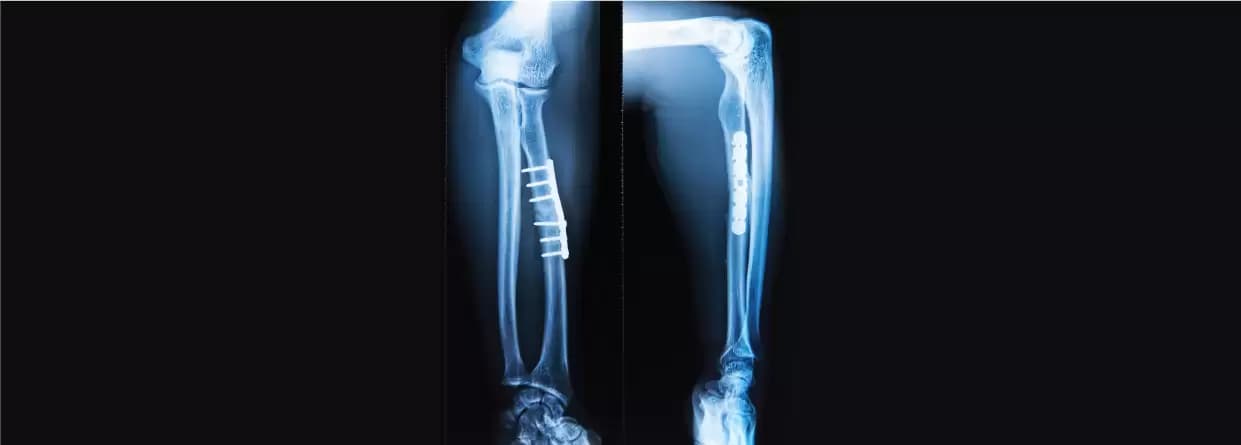

It is one of the treatment methods that the doctor will include. It is recommended when the bones haven’t moved out of their places and the fracture is minor. To treat the problem, there might be a requirement for a cast or splint only. Splinting lasts for more than three to five weeks whereas cast is longer i.e.eight weeks. For both, the doctor will order x-rays to ensure that transverse process fracture recovery is going fine.

The doctor will recommend the following surgery option for transverse process fracture: